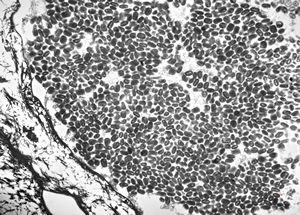

F, 7y. | molluscum contagiosum … virions

F, 7y. | molluscum contagiosum … virions